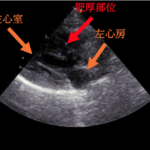

- 猫の肥大型心筋症、拘束型心筋症、動脈血栓塞栓症